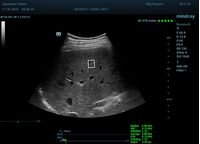

Определение плотности печени. Не ошибся ли оператор при измерении эластических свойств печени? Для оценки критериев качества предусмотрен индекс MBT, который покажет насколько «твердой» была рука оператора и двигалась ли печень. При MBT 5* рука тверда и показатели достоверны. Для оценки качества результатов используется IQR индекс, отображающий колебания показателей в точке измерения при расчете медианы. Показатели при IQR <30% считаются приемлемыми. Техника сканирования через межреберные промежутки требует размещение окна интереса на несколько сантиметром ниже капсулы, для исключения эффекта реверберации. Установка ROI на паренхиму без захвата сосудов, для исключения погрешностей измерения.